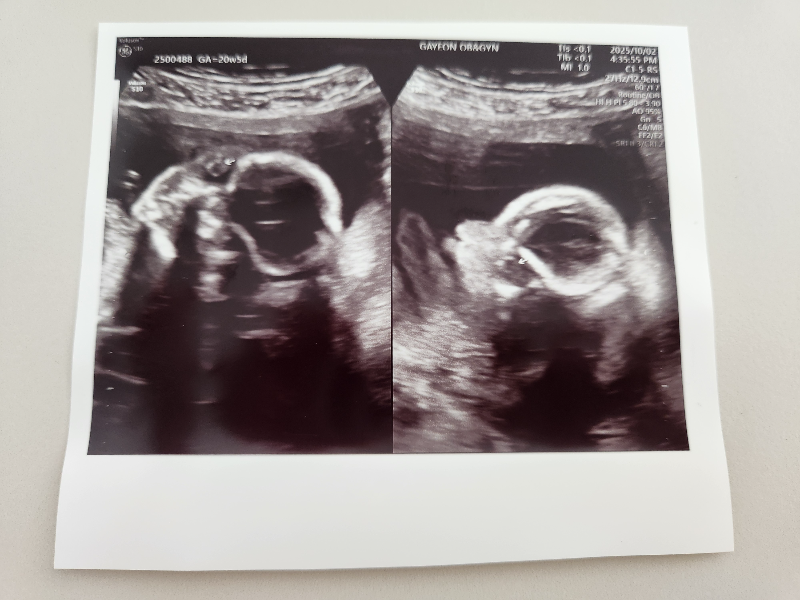

2차 정밀 초음파는 입체로도 봐주십니다.

태아가 손을 올리고 있어서 잘 안 찍혔지만, 이제 사람이 된 것 같습니다.